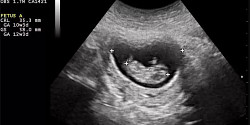

18 janvier 2023Étude en échocardiographie foetale - Dr Frédéric Dallaire et son équipe

Recherches de l'année en santé selon La Presse